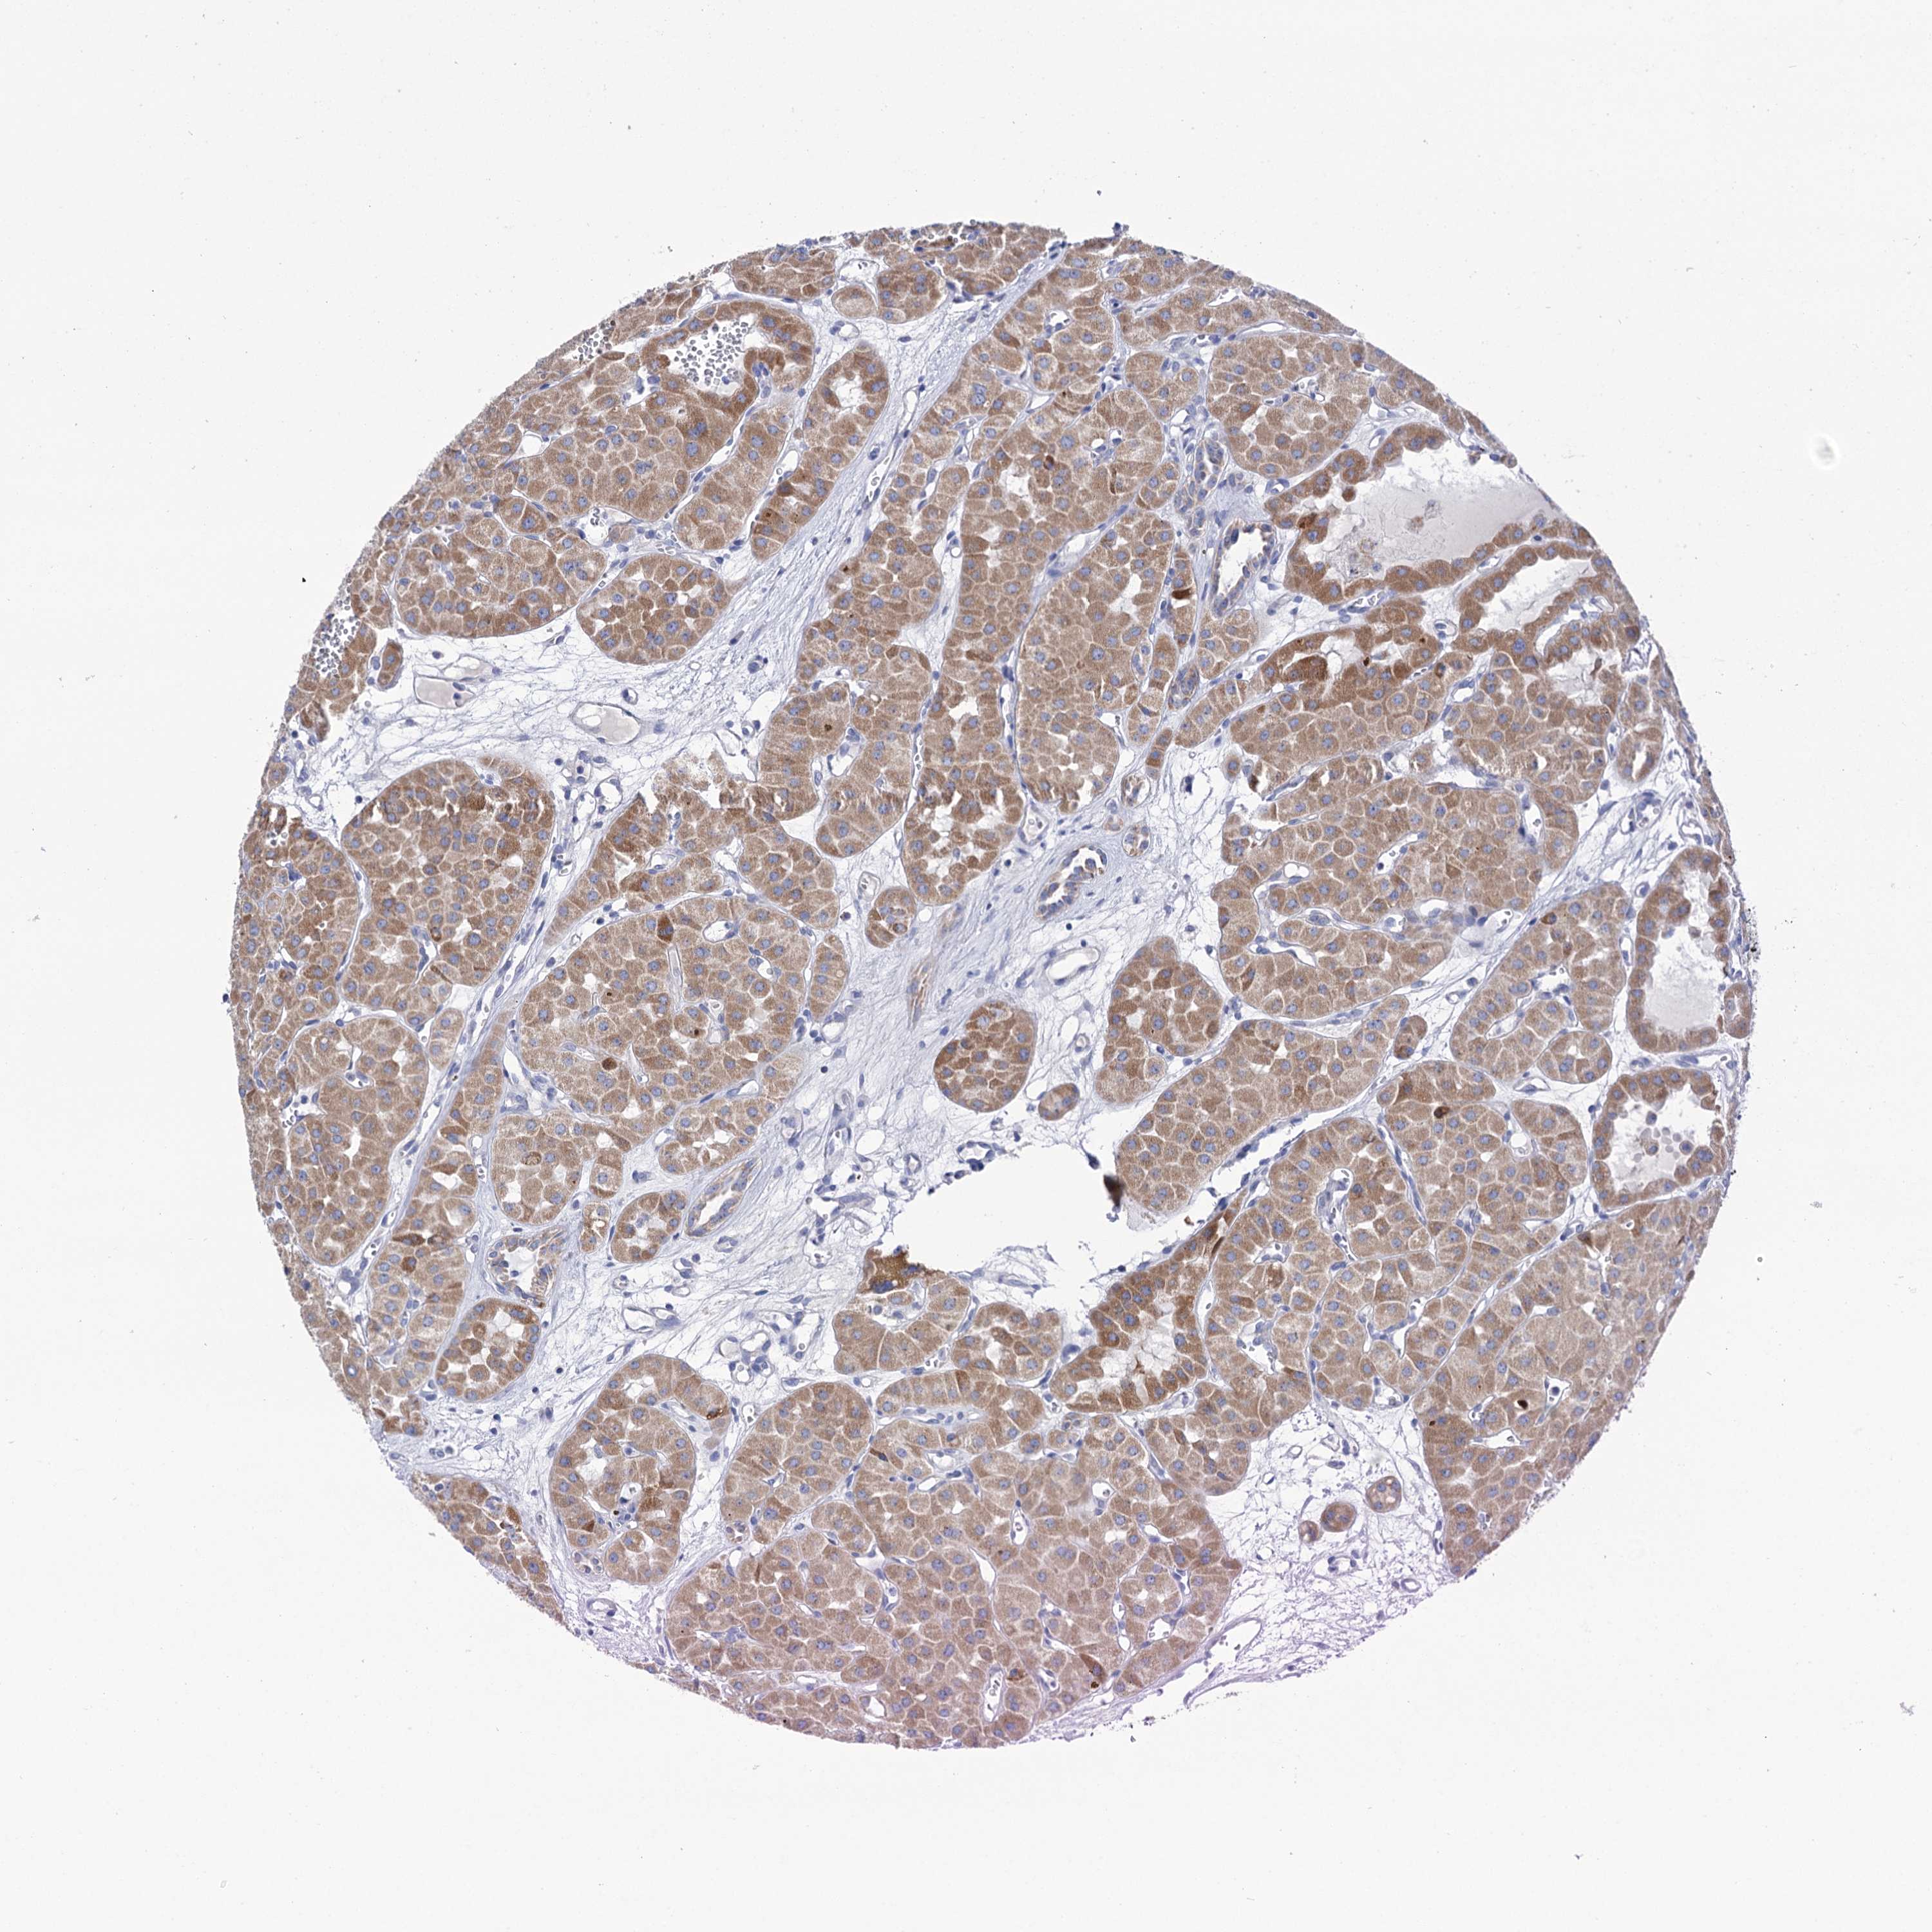

CANCER RENAL CANCER Show tissue menu

KICH TCGA KIRC TCGA KIRC VALIDATION KIRP TCGA PROTEIN RCC CPTAC PROTEIN EXPRESSION